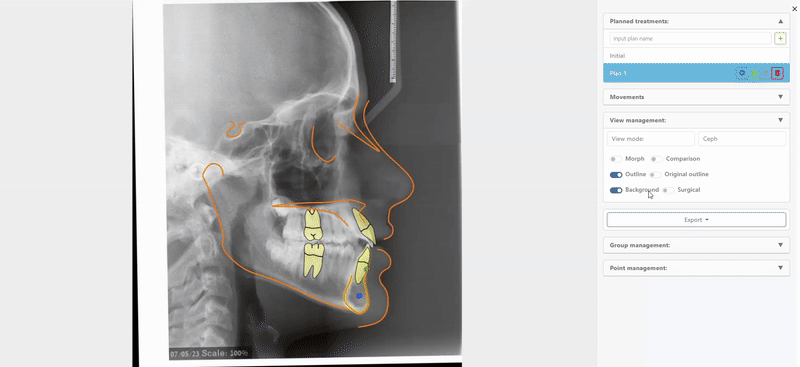

Visual Treatment Objective (VTO) & Surgical Treatment Objective (STO)

A next-generation feature – the VTO, turns a standard 2D cephalometric X-ray into a dynamic, interactive planning tool that lets clinicians simulate and visualize orthodontic or surgical treatment outcomes directly on the image. It helps predict jaw and tooth movements, visualize soft tissue changes, and compare different treatment scenarios, making it easier to communicate plans clearly and confidently. By bridging the gap between diagnosis and patient understanding, VTO makes treatment planning more precise, visual, and intuitive.

How Does It Work?

Once you click the VTO feature, the right panel lets you move and rotate teeth and jaws with precise controls and optional soft-tissue simulation. They can switch between Ceph, Morph, and comparison views, export images/PDFs/animations or save cases, and edit key cephalometric points and groups.